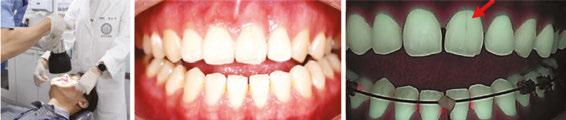

Figures 3A-3B: Pre-orthodontic crack assessment was conducted using Q-ray Cam and Q-ray PenC. 3A. In a 20-year-old female patient, frontal intraoral imaging with Q-ray Cam detected a crack on the maxillary left central incisor. Consequently, orthodontic appliance placement was postponed and limited to an 8-month duration. 3B. Q-ray PenC allowed precise evaluation of the posterior molars, revealing a clear crack line in a clinically intact restored molar not detectable by conventional visual inspection